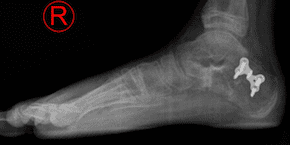

The image above compared to the image on the left, demonstrates a flat foot reconstruction achieved through bony procedures and is aimed at restoring the arch and maintaining joint motion.

Arthroreisis Procedure

This procedure is also reserved for flexible flat feet and typically is performed in teenagers that suffer from flat feet. The older the person becomes, the less tolerable the procedure becomes. This is a procedure that involves placing a metallic or plastic absorbable implant in the sinus tarsi(space between the two bones in the back of the foot that dictate the position of the foot – pronation vs supination) This device causes a blockade that realigns the foot and prevents the collapse of the foot.